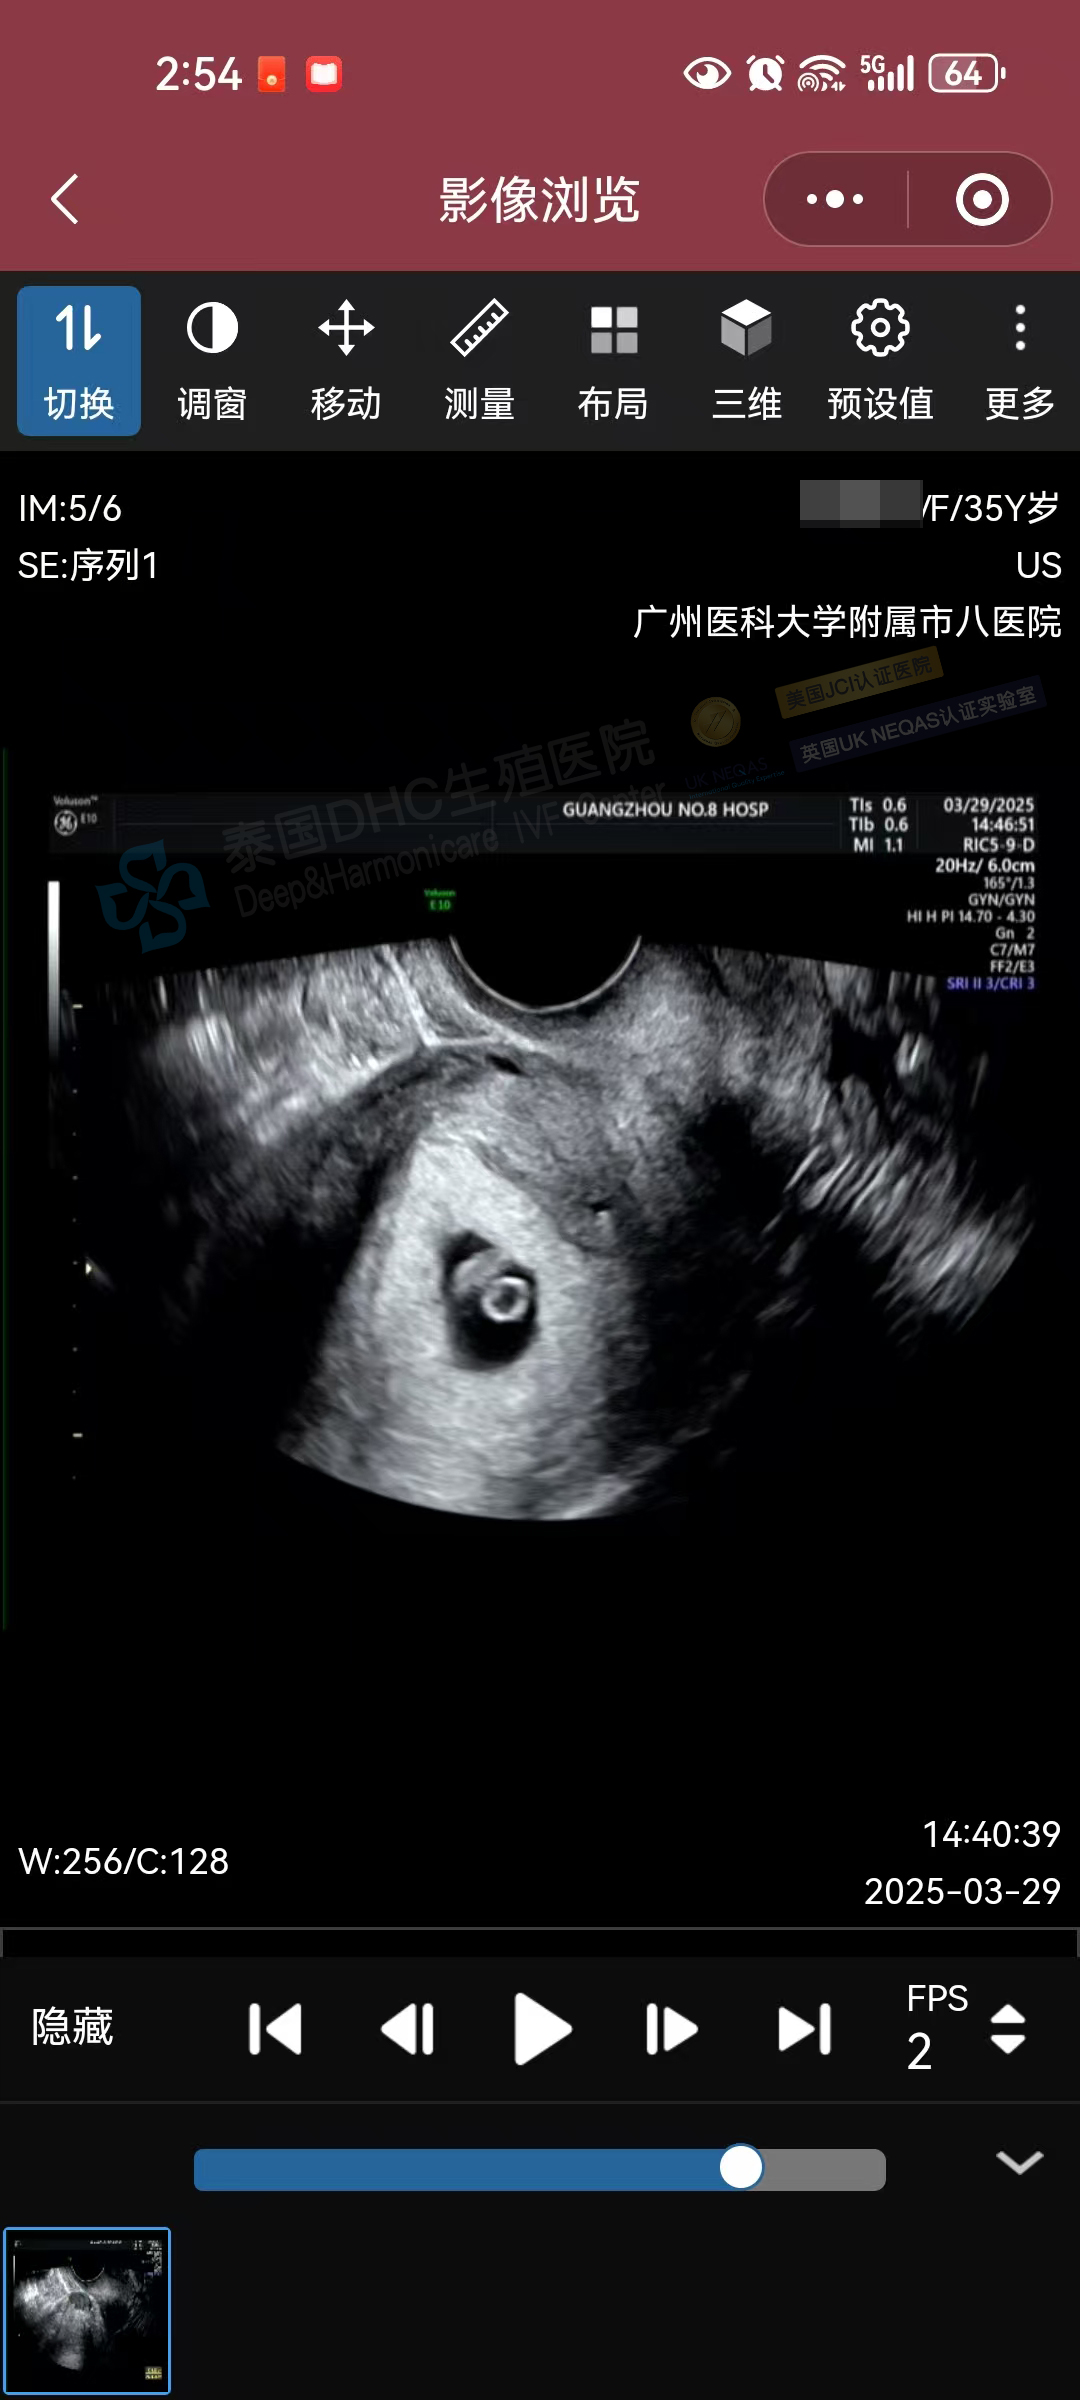

生命奇跡,如期而至!DHC三代試管助孕的35歲準媽媽今日復查B超,再次迎來喜悅——小小寶貝胎心有力跳動,宣告著新生命的茁壯成長!?

大齡客戶優選基因備孕二胎,在中泰一體化診療模式下,通過助孕寶+中西醫+營養師等綜合調精養卵助攻后,順利進入試管周期,6枚囊胚篩查100%通關!恭喜客戶,科學備孕成功率棒棒噠。